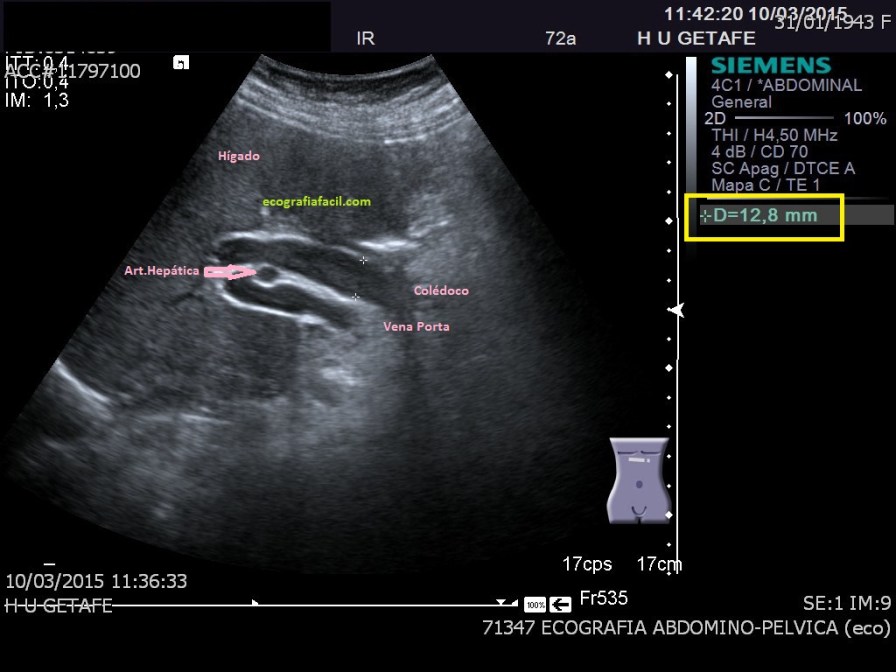

Cuando hablamos del Hilio Hepático, hablamos de una porción anatómica muy importante desde le punto de vista de la exploración ecográfica dentro del protocolo de Abdomen. La imagen que te pongo a continuación es difícil de conseguir, técnica y anatómicamente, pero a veces, nos encontramos este corte parasagital que nos da una información fabulosa y una correlación anatómica perfecta del la vía biliar extrahepática, arteria hepática y vena porta.

Hoy nos vamos a parar exclusivamente en la consecución de esta imagen, que depende de cada paciente, será un corte parasagital y la conseguiremos en decúbito lateral izquierdo. No es vinculante la imagen del pictograma que aparece en la imagen, cada paciente necesitará una orientación, este concepto es vital.

Este corte es un corte parasagital, donde el transductor está paralelo tanto al eje largo de la porta como al eje largo de la vía biliar extrahepática, que como vimos muchos capítulos atrás son paralelas, siendo la vía biliar extrahepática anterior a la porta, siendo la porta, referencia para buscar la vía biliar.

Entre ambas discurre, perpendicularmente, la arteria hepática. Por eso en este corte nos la vamos a encontrar como una circunferencia, entre dos estructuras tubulares.Es una imagen de una belleza brutal, difícil de conseguir, ya digo, pero debemos buscarla siempre.

La relación anatómica de la ecoestructura es esta. Observa la medida, marca una elevación anormal de los estándares de medición para la vía biliar extrahepática o colédoco, si a estos pacientes con esta medida del colédoco no les encontramos causas justificadas para esta dilatación, acabarán haciéndose una Colangio Resonancia Magnética para demostrar la causa de dicha dilatación, patológica, según la literatura, por encima de 1 cm, considerando que cada 10 años que cumplimos, nuestra vía biliar extrahepática puede aumentar 1 mm. Es decir, para un/a paciente de 40 años, la normalidad de esta medida será en torno a 0,4 cms, para uno de 70, 0,7 cms, en este caso, de 72 años, mide 12,8 mms, claramente anormal.

Las causas de esta dilatación son variadas, desde colédocolitiasis hasta tumoraciones de la cabeza pancreática, por eso es vital el estudio de dicha región con minuciosa rigurosidad.

Algunxs pacientes con patología son asintomáticxs, además debemos saber que en pacientes colecistectomizadxs podemos encontrar dilataciones de calibre superior al estándar y ser normales.